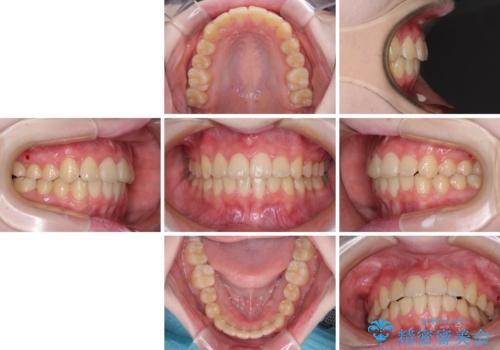

前歯をきれいに整えたい ワイヤー装置での非抜歯矯正

治療途中で大学受験があり、来院できない時期がありましたが、2年以内で満足のいく歯並びを達成することができました。